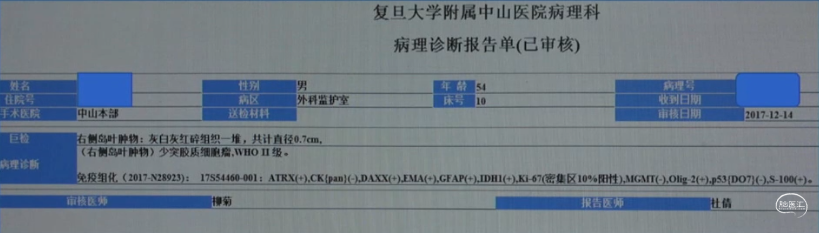

术后病理

少突胶质细胞瘤(WHO Ⅱ级)